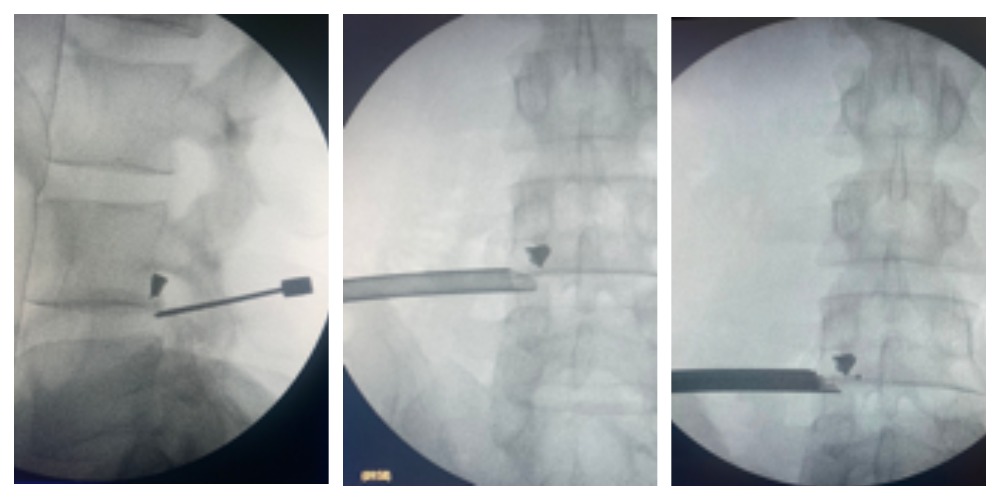

Выполнена операция: эндоскопическое удаление инородного тела (осколка) из межпозвонкового отверстия на уровне LIV-LV слева.

Рисунок 3. Этапы выполнения эндоскопического доступа к металлическому осколку